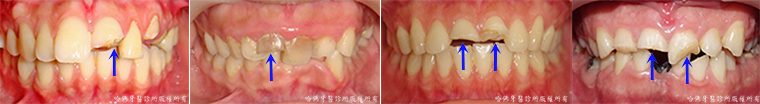

齒列不整,特別是存有牙齒擁擠的齒列不整,極易造成食物堆積的死角而引發蛀牙(圖2)。

(圖2)齒列不整,特別是存有牙齒擁擠的齒列不整,極易造成食物堆積的死角而引發蛀牙。藍色圈標定蛀牙位置。

當蛀牙尚在輕微的時候缺乏臨床症狀,蛀牙經常在嚴重時才出現酸痛腫脹等症狀。而當酸痛腫脹等症狀出現時,蛀牙已相當嚴重「而不」易治療(圖3)。

(圖3)當蛀牙尚在輕微的時候缺乏臨床症狀,蛀牙經常在嚴重時才出現酸痛腫脹等症狀。而當酸痛腫脹等症狀出現時,蛀牙已相當嚴重「而不」易治療。